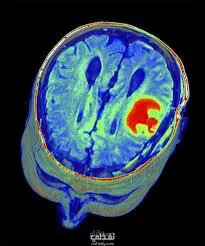

نبذة عن المشروع: تطوير نظام تعلم عميق متكامل ودقيق لتحديد وتقسيم أورام الدماغ من صور الرنين المغناطيسي (MRI) متعددة القنوات. تم تصميم النظام للتعامل مع تحديات البيانات الطبية المعقدة، وبناء خط أنابيب (Data Pipeline) قادر على معالجة واستيعاب مجموعة بيانات ضخمة جداً بكفاءة عالية. التحدي التقني: تمثل التحدي الأكبر في معالجة مجموعة بيانات طبية ضخمة بحجم 116 جيجابايت، تتكون من صور ثلاثية الأبعاد (3D NIfTI) بأربع قنوات مختلفة (T1, T1ce, T2, FLAIR)، وتجهيزها بكفاءة لتدريب نموذج الذكاء الاصطناعي دون استنفاد موارد النظام، مع حل مشكلة عدم توازن الفئات (Class Imbalance) في الأورام. التقنيات والخطوات المتبعة: هندسة البيانات الضخمة (Data Engineering): معالجة الـ 116 جيجابايت من البيانات الطبية من خلال تطبيق تقنية (Z-Score Normalization) على مستوى حجم الدماغ بالكامل لتوحيد التباين، واستخراج الشرائح ثنائية الأبعاد (2D Slices) بكفاءة لتسريع عملية التدريب. معمارية المحولات (Swin-UNet): بناء نموذج يعتمد بالكامل على تقنية (Vision Transformers) بدلاً من الشبكات الالتفافية التقليدية (CNNs)، مما ساعد في التقاط التفاصيل الدقيقة للسياق العام للورم بفضل آلية الانتباه (Shifted Window Attention). تحسين البيانات (Data Augmentation): استخدام مكتبة Albumentations لتطبيق تحويلات هندسية متقدمة تناسب الأنسجة الطبية (مثل Elastic Transforms و Grid Distortions) لزيادة متانة النموذج ومنع الحفظ الأعمى. دالة الخسارة المخصصة: استخدام (Categorical Focal Loss) لإجبار النموذج على التركيز على الأجزاء الصعبة من الورم والتغلب على مشكلة عدم توازن الفئات، وتقييم الدقة باستخدام مقياس التطابق (Dice Score). المعالجة اللاحقة (Post-Processing): برمجة خوارزميات الفلاتر المورفولوجية لتنظيف النتائج وسد الفجوات الخاطئة (False Negatives) بحجم أقل من 300 بكسل بذكاء، مما رفع من دقة التحديد النهائي بشكل ملحوظ دون التأثير على الأنسجة الميتة الحقيقية (Necrotic Core). الأدوات والتقنيات المستخدمة: Python, TensorFlow / Keras, OpenCV, Albumentations, Nibabel, Scikit-Image.